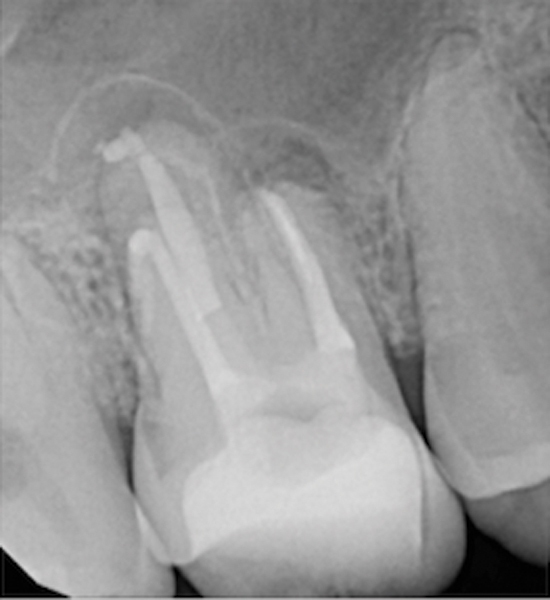

Fig 15. Preoperative radiograph. Courtesy of Dr. Sam Kratchman.

Figure 15

Fig 16. Post apicoectomy. Courtesy of Dr. Sam Kratchman.

Figure 16

Fig 17. Retropreps and isthus filled. Courtesy of Dr. Sam Kratchman.

Figure 17

Fig 18. 20-month follow-up with BC putty shows complete healing. Courtesy of Dr. Sam Kratchman.

Figure 18

Case 3: Apicoectomy and Retrofill

A patient presented with clinical symptoms and radiographic signs of post-endodontic disease (Figure 15). It was determined that the ledge on the mesial canals precluded retreatment and that an apicoectomy was to be performed. After locating the apicoectomy, it was possible to visualize both canals and an obvious isthmus between the two main canals (Figure 16). Retro-preparations were performed in the main canals, and the isthmus between them was grooved and the cavities filled with BC RRM-Putty (Figure 17). At the 20-month follow-up, the patient was asymptomatic and the radiograph showed complete healing (Figure 18).